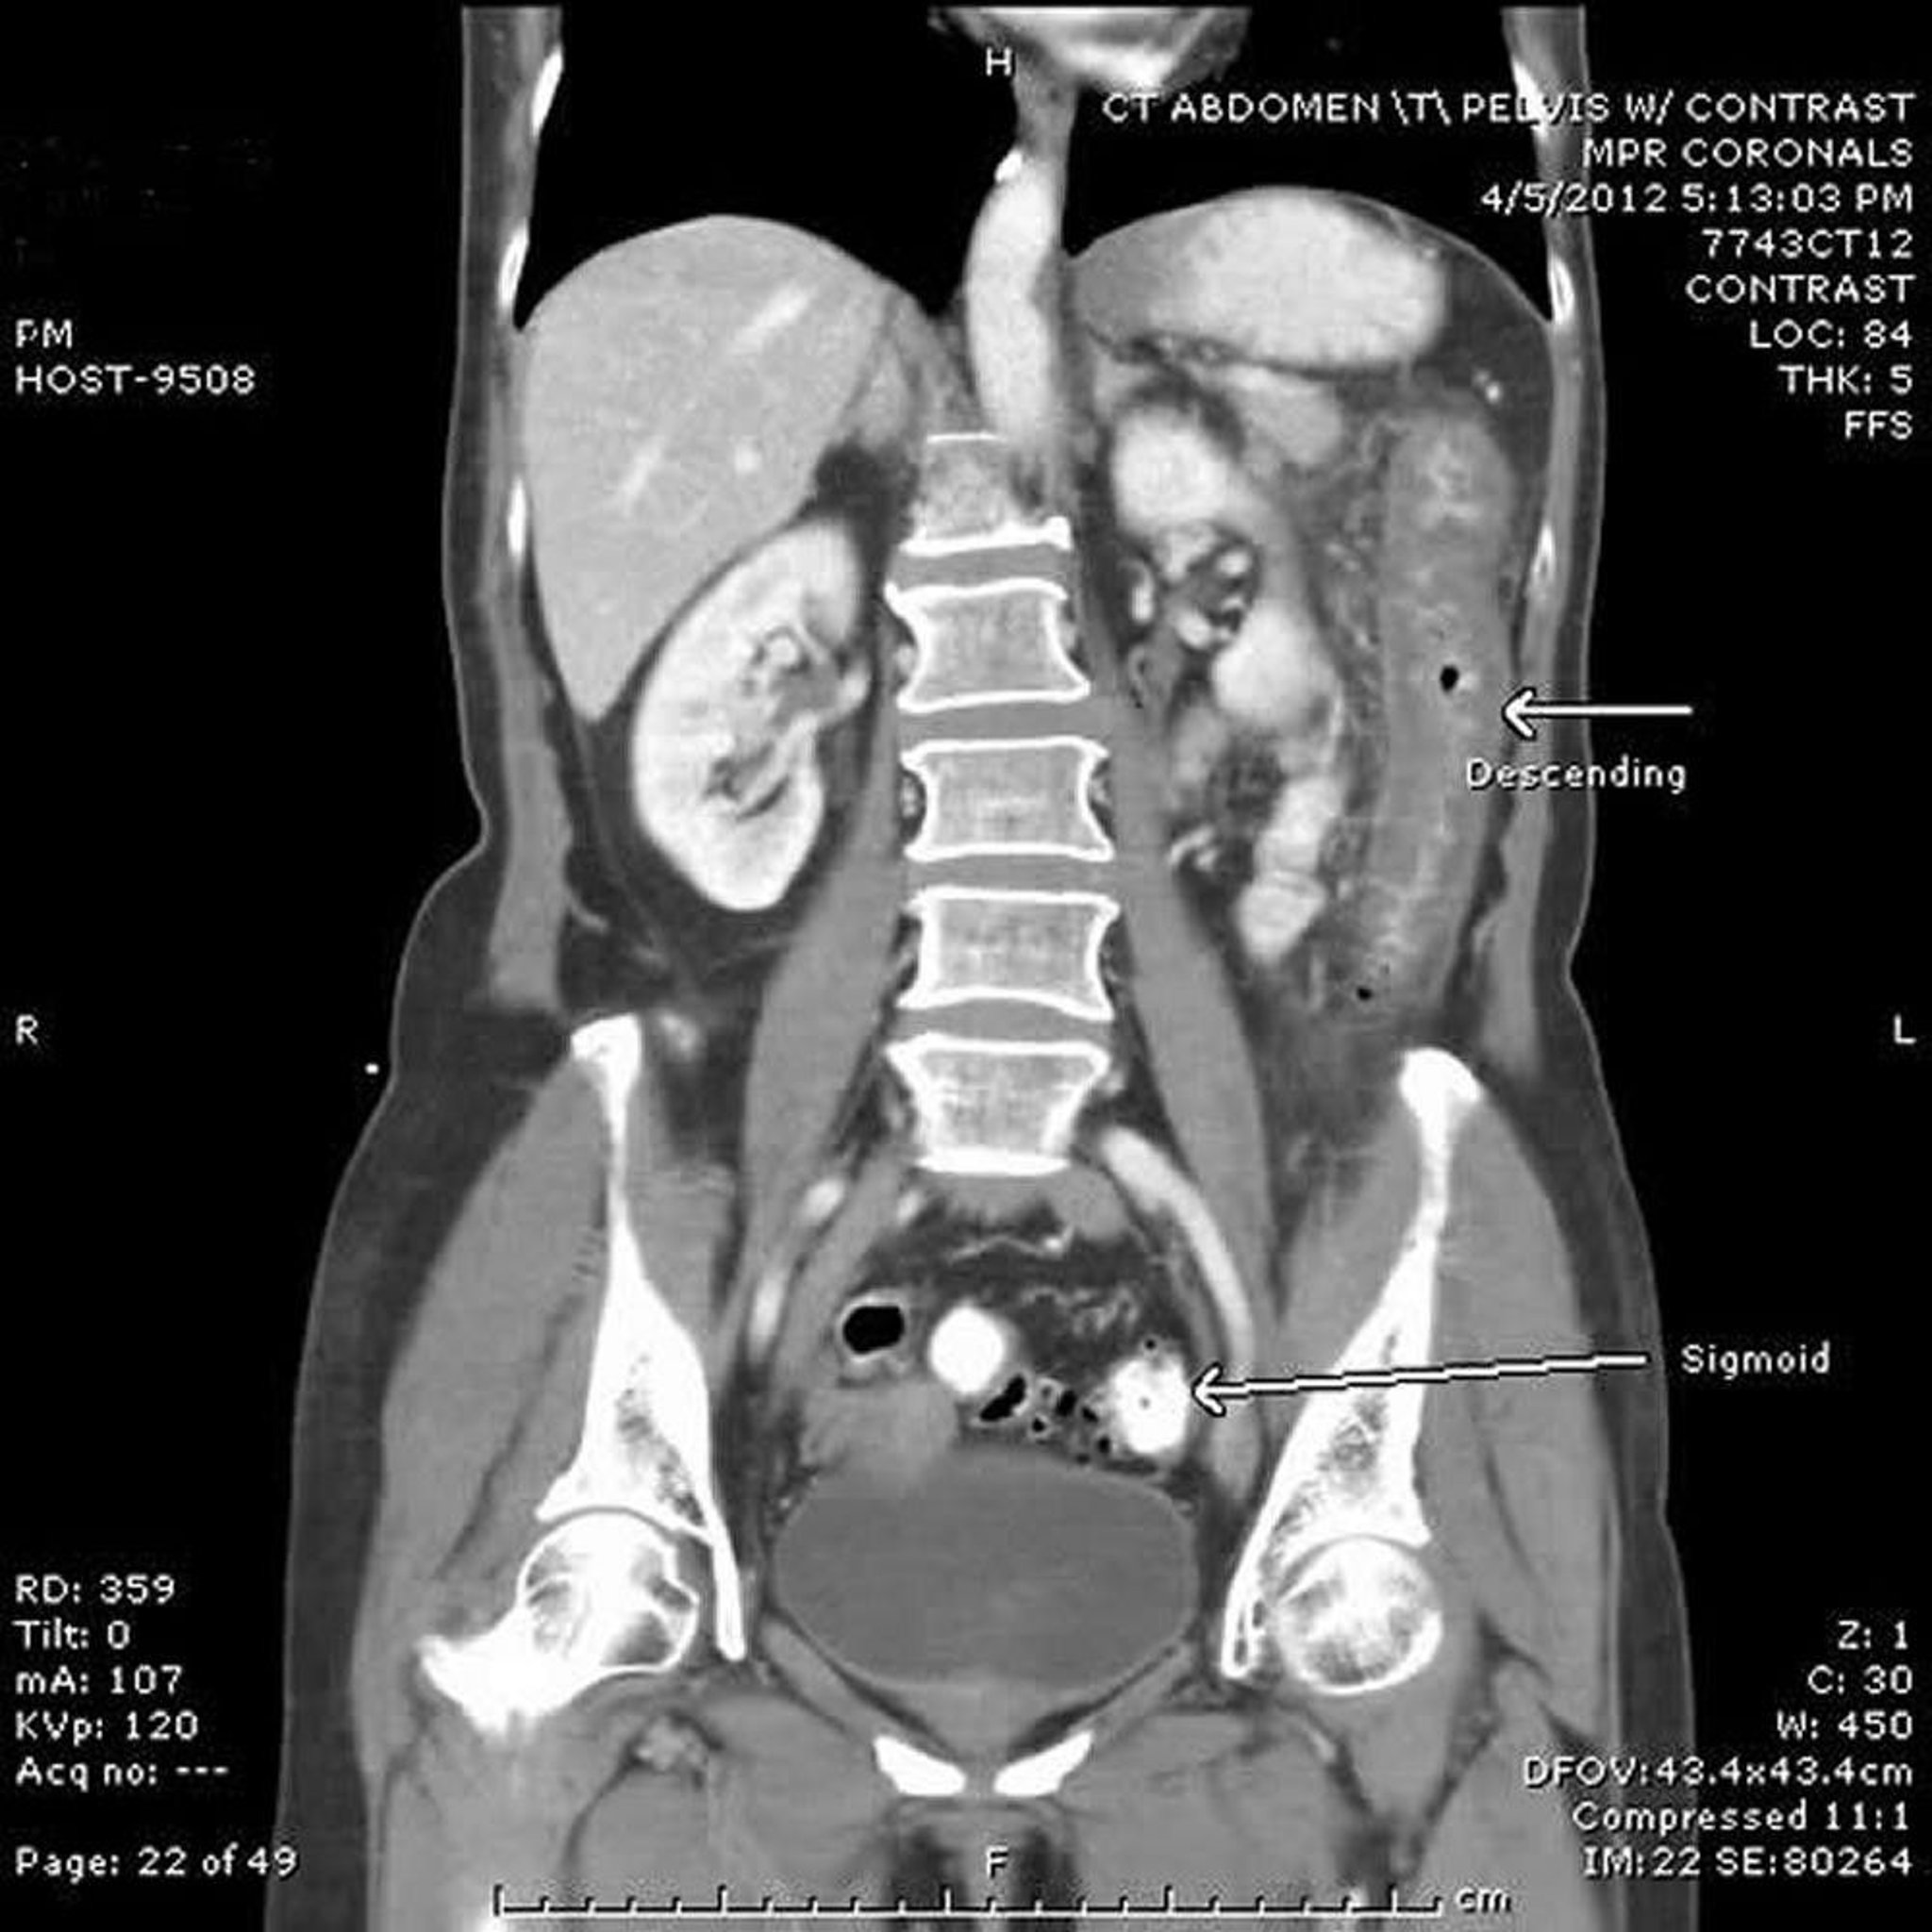

Ischemic Colitis (CT Scan)

In this CT scan, the descending colon (top arrow) is thick-walled from the splenic flexure to the proximal sigmoid colon. Note the distal sigmoid colon (bottom arrow) with diverticulosis but without inflammatory or ischemic changes.

Image provided by Parswa Ansari, MD.